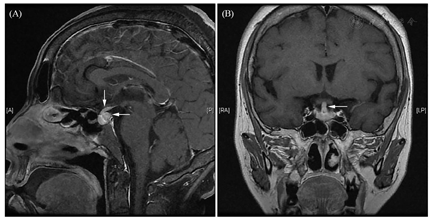

影像学资料:鞍区MRI平扫+增强提示垂体后叶及垂体柄信号异常(图1)。甲状腺超声:甲状腺实质弥漫性病变,不除外桥本甲状腺炎。全身浅表淋巴结超声波检查提示双侧锁骨上区多发稍大淋巴结,右侧大者1.0 cm×0.7 cm,左侧大者0.9 cm×0.7 cm。肺CT:右肺下叶背段空洞合并双肺多发性结节影(图2)——化脓性感染、肺脓肿?经CT引导下右肺下叶结节穿刺活检,病理学检查结果回报:肺间隔明显增宽,部分实变,伴大量淋巴细胞、浆细胞及少许嗜酸性粒细胞浸润(图3)。免疫组化染色提示CD138+、IgG4+,部分热点区域IgG4+细胞约为40个/高倍视野。特殊染色:弹力纤维+,革兰氏-,PSA-,PASM-,黏液卡红-。请结合临床除外IgG4相关性疾病(IgG4-related disease, IgG4-RD)。未见明确真菌、结核及肿瘤性病变。腹部CT未见异常。

本例患者主要表现为中枢性尿崩症,其鞍区MRI提示垂体柄增粗、垂体后叶亮信号消失。同时合并肺内多发结节病变、桥本病、淋巴结肿大,化验检查提示IgG4为2.87 g/L,右肺下叶结节穿刺活检病理学检查示大量淋巴细胞、浆细胞及少许嗜酸性粒细胞浸润,免疫组化染色提示IgG4+细胞约为40个/高倍视野,因此诊断为IgG4-RD。